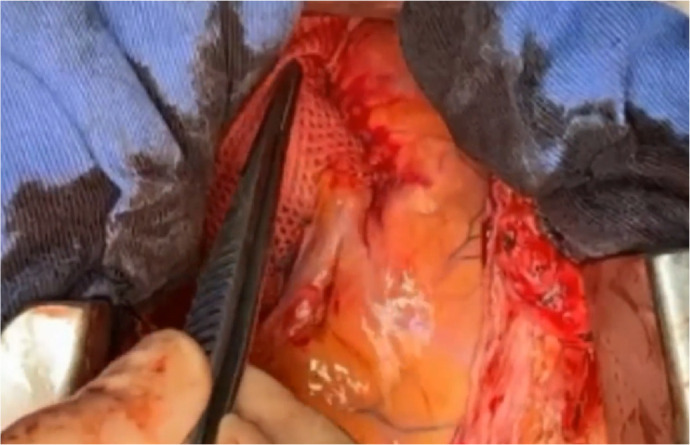

Methods: This report presents the initial clinical experience with the ExoVasc® PEARS implant in the Americas, encompassing 10 patients (six males, age range 30 - 52 years, mean age 37.8 years) diagnosed with aortic root aneurysms. Indications for PEARS included Marfan syndrome (eight patients, including one reoperation), bicuspid aortic valve (two patients, including one with anomalous coronary artery), and associated valvular dysfunction. Cardiopulmonary bypass was utilized in four cases.